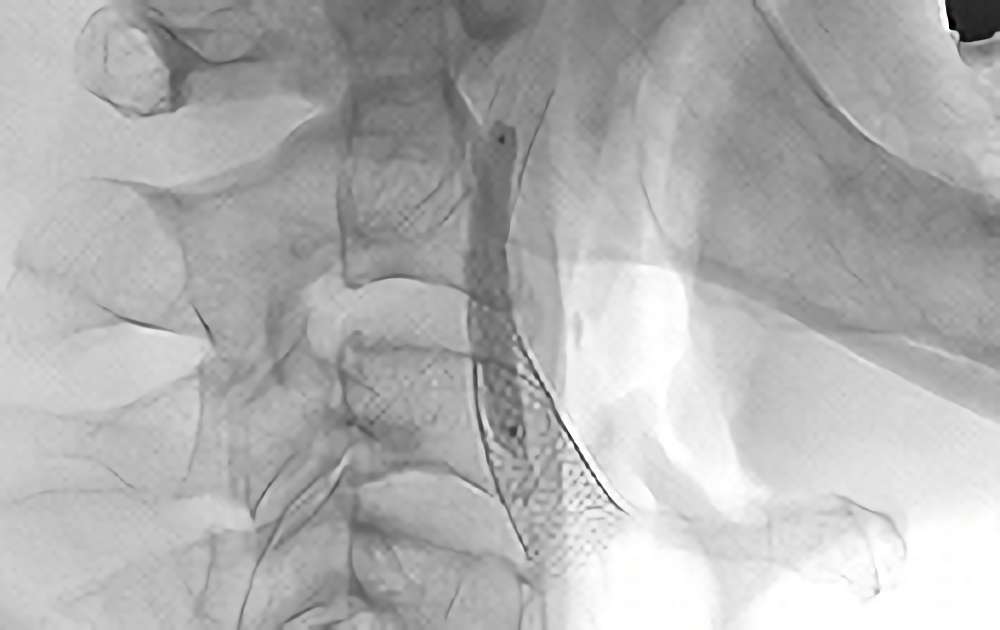

855

'20年7月15日

左内頚動脈狭窄症

70代

大阪府の病院

手術写真

'20年7月